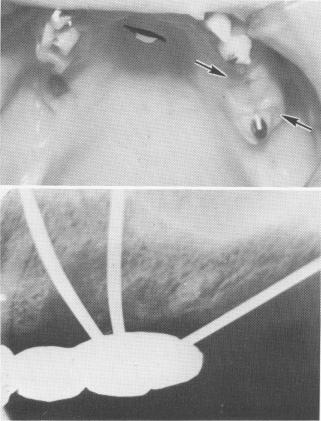

Fig. 14-38. A, The soft tissue directly surrounding the blade implant is compressed (arrows) because of poor pontic relationship. The tissues can become mutilated and inflamed if this is not alleviated. B, Triplants were forced through improperly sized and directed holes in the template (the holes were too small). This caused a torque action on the template and on the pins themselves (notice how pins are curved in bone), which led to bone destruction.

1 Tissue surrounding dental blade compressed due to poor pontic relation

2 Triplants forced through improperly sized holes in maxillary template